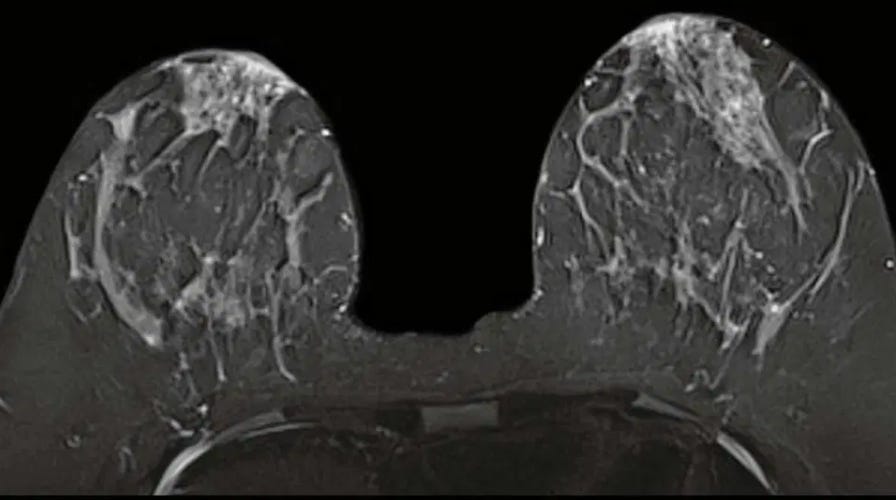

For example, imagine that a clinician has ordered a breast MRI for a patient with dense breasts, for which standard mammograms are notoriously unreliable. In today’s system, the physician or her staff would need to write up a prior auth request, manually enter the relevant patient history and prior testing information, fax the form to the insurance company, and wait a week or two for an answer.

Now consider a future system in which AI-infused prior authorization was integrated into the EHR. If the insurer’s criteria for approving the MRI included a prior mammogram showing dense breasts and limited interpretability – and let’s be sure we continue to have humans with both content knowledge and a functioning ethical compass setting these criteria – the AI would review the chart looking for evidence of that test and the radiologist’s interpretation. Failing to find it, the system would ask for such documentation, and, if none were available, automatically “tee up” a mammogram order directly in the EHR for the physician to consider. The process could be completed in minutes.